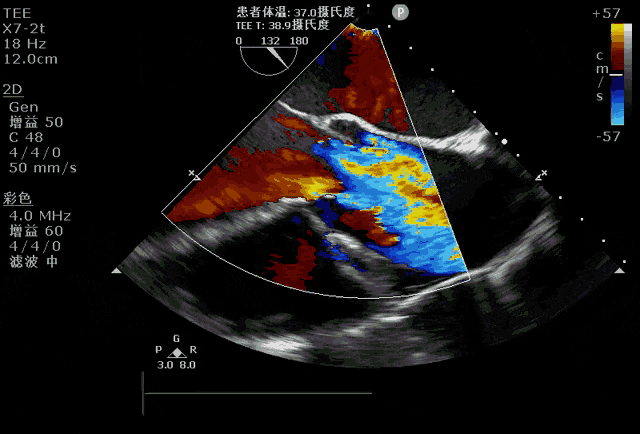

首先,心脏彩超,即超声心动图,是一种非侵入性检查方法,通过超声波来观察心脏结构和功能。

具体来说,心脏彩超能够检查心脏的大小、形态、壁运动、瓣膜功能以及血流情况等多个方面。

这对于发现心脏结构方面的异常,比如心脏肥大、瓣膜病变等具有重要意义。

而且,心脏彩超还可以评估心脏的血流动力学状态,帮助医生判断是否存在心脏功能方面的问题,比如心脏收缩功能是否受损、是否存在异常的血流方向等。